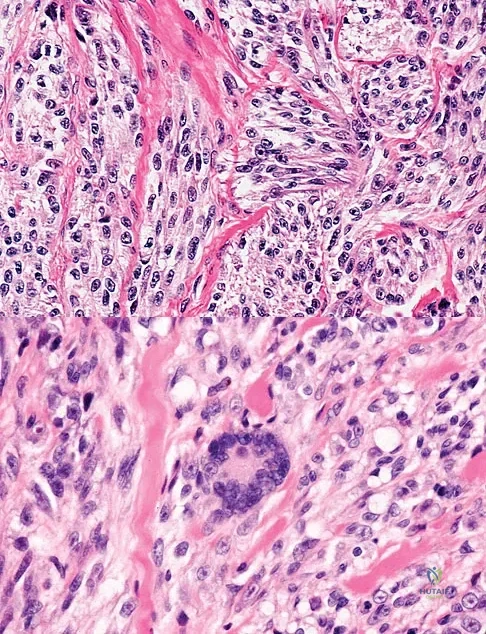

Question 45

A 35-year-old man reports the development of a painful 2-cm nodule on his dorsal wrist over the past 3 years. A surgeon excised the lesion with a presumptive diagnosis of a ganglion cyst. Histology sections from the excision are shown in Figures 11a and 11b. What is the most likely diagnosis?

Explanation